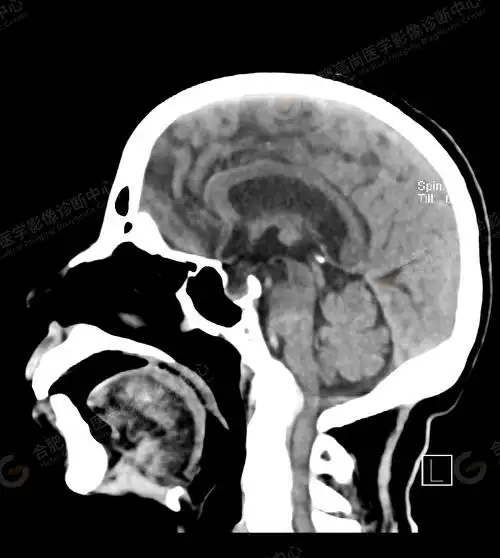

67超急性期大面积脑梗死ct平扫表现